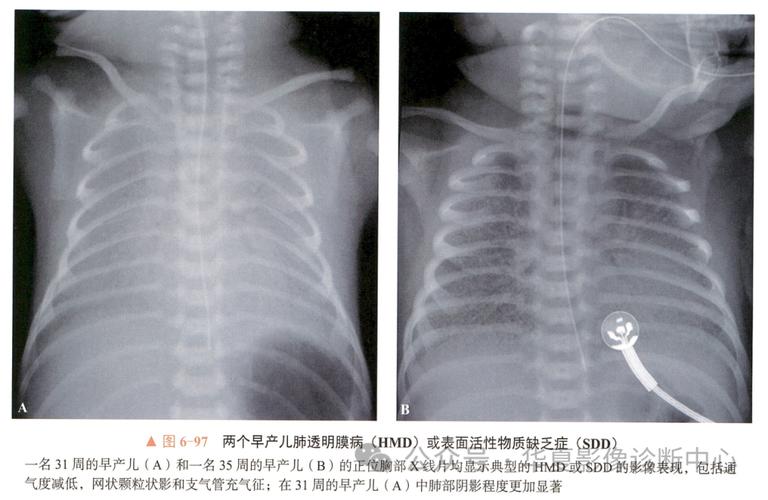

新生儿肺透明膜病的X线表现具有特征性,主要反映了肺泡萎陷、肺泡管和终末细支气管扩张以及支气管充气征的病理生理改变,其严重程度与病程进展密切相关,因此X线检查不仅是诊断的重要依据,也是评估病情和指导治疗的关键手段。

肺野呈“毛玻璃”样改变

这是疾病早期或轻度的典型表现。

- 成因:广泛的肺泡萎陷导致肺的含气量显著减少,而肺泡管和终末细支气管因过度扩张而充满了空气,这两者形成了密度不均匀的影像,透过这层“不均匀的肺”可以看到含气的肺血管影,整体外观如同磨砂玻璃或毛玻璃。

- 特点:肺野透亮度普遍性降低,但并非完全均匀一致,内部可见模糊的网状或颗粒状结构。

支气管充气征

这是最具特征性的X线征象,在毛玻璃背景上尤为明显。

- 成因:由于肺泡萎陷塌陷,而中央的气管、支气管分支仍保持通畅并充满空气,在密度增高的肺野衬托下,这些充气的支气管树分支被清晰地勾勒出来,形成“树枝状”或“轨道状”的影像。

- 特点:从肺门向外延伸的、分支状的透亮影,在毛玻璃样或白色的肺背景下非常醒目。

(图片来源网络,侵删)

(图片来源网络,侵删)- 特点:表现为局灶性或弥漫性的斑片状、云絮状阴影,分布不均,可合并胸腔积液,支气管充气征也可能出现,但背景不是均匀的毛玻璃样。

新生儿肺透明膜病的X线表现是一个从颗粒状阴影 → 毛玻璃样改变 → 白肺的动态演变过程,支气管充气征贯穿其中,是其最具特征性的标志,放射科医生和临床医生通过分析这些X线征象的严重程度和动态变化,能够快速准确地诊断HMD,评估病情,并为制定呼吸支持方案(如是否使用肺表面活性物质PS)提供关键的影像学依据。